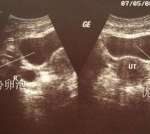

不孕症需要做所有相关检查,如精液常规检查、女性内分泌检查、排卵检查、子宫内膜及输卵管检查等。这也是试管婴儿之前的必考项目,所有生化检查,免疫系列检查等。

1.术前检查。一般在试管婴儿治疗前,夫妻双方都要进行术前检查,主要是排除一些不适合试管婴儿的疾病,比如传染病,不适合女方怀孕的疾病,费用大概在人民币左右。2.试管婴儿的药费。试管婴儿女方的卵子是药物诱导排卵后取出的,所以一般要用20-40个促排卵药物,加上之前用过的降调节药物,一共花了人民币。3.试管婴儿取卵、培养、移植费用。如果有多余的好胚胎,要冷冻保存,大概1万元左右。比如做精子注射(ICSI),大概要2000元左右。这样算下来,三部分的总费用大概在2万到3万元,当然是因为地区差异。

卵巢早衰很难做试管婴儿,因为卵巢本身分泌的激素不足,不能支持胎儿的生长发育。就是不能正常排卵,这是卵子质量的问题。如果年龄不是很大,还有希望,需要去专门的生殖中心进行专科治疗。外源性补充可以促进排卵。